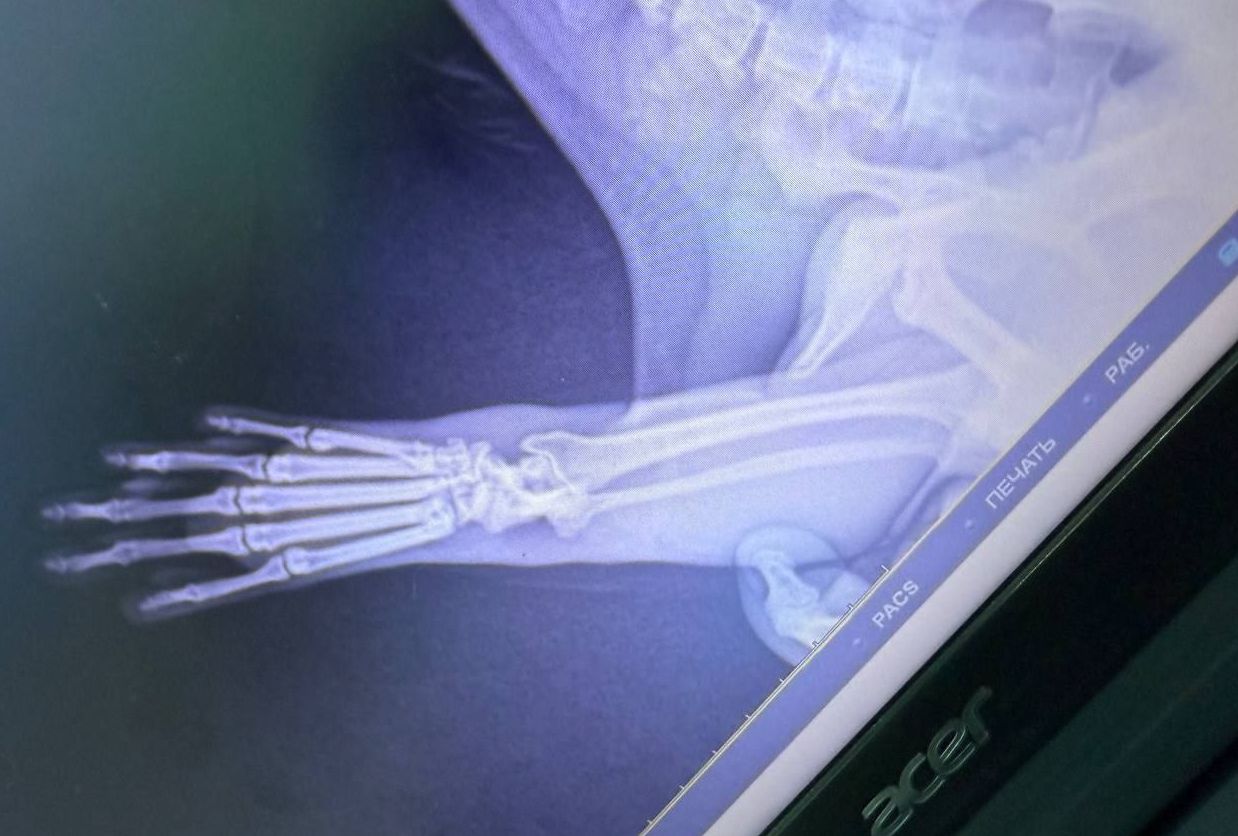

Сразу же начались консультации с коллегами из Москвы и Санкт-Петербурга, и океанариума ветеринар Валерия, посовещавшись со специалистами, приняла решение – Тоню нужно везти на рентген. А вдруг перелом? Мысль об операции пугала всех.

Какое же облегчение испытали все, когда узнали диагноз – вывих. Операции не потребуется! Тоня – настоящая молодец, держалась спокойно, видно, чувствовала, что Сергей и Валерия рядом.